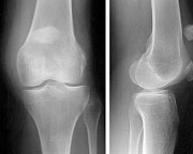

Fracturas del tercio superior de la tibia

Las fracturas en el tercio superior de la tibia suponen el 1% de todas las fracturas y el 8% de las fracturas del anciano. Están causadas por fuerzas violentas que producen desviaciones laterales sobre la rodilla. La osteoporosis en el paciente de edad facilita estas fracturas. Son lesiones que también vemos en el ámbito deportivo fundamentalmente en aquellos deportes que exigen un sobreesfuerzo de la articulación de la rodilla como el esquí, el fútbol o el patinaje. En los deportistas suelen acompañarse, además, de lesiones ligamentosas que pueden pasar desapercibidas si no se realiza una exploración exhaustiva.

El tratamiento de las fracturas del tercio superior de tibia es quirúrgico con la finalidad de devolver a la rodilla su anatomía normal para el rápido inicio de la movilidad articular. Los avances en técnica artroscópica y los nuevos implantes permiten el tratamiento de estas fracturas de una forma poco agresiva y fiable que disminuye las complicaciones postoperatorias y agiliza el tiempo de recuperación.